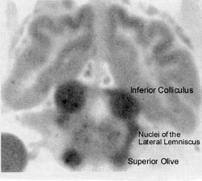

Figure

6 is an autoradiogram from the experiments

on cerebral blood flow in cats.  It was published in an

article by Seymour Kety, who was the principal

investigator of these experiments [6].  The blood flow

data from the same research is shown in table 3.

The highest blood flow

and metabolism in the brain is

in the brainstem nuclei of the

auditory pathway.

Landau et al (1955) used a

radioactive tracer to investigate

cerebral blood flow in laboratory

animals [1]. The picture to the

left is an autoradiogram of the

brain of a cat 60 seconds after

injection of a tracer.  It shows

the greatest perfusion (thus

greatest blood flow) in the

inferior colliculi, superior olives,

and lateral lemniscal tracts

connecting these relay nuclei in

the brainstem auditory pathway.